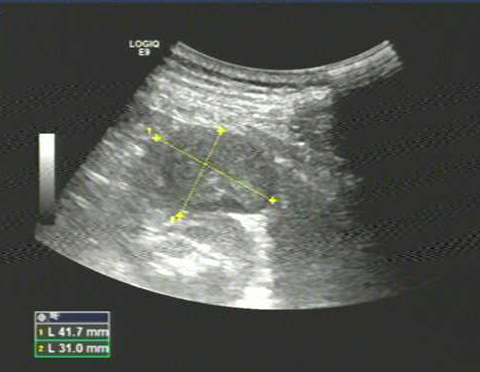

XXX,女,41Y,体检发现左肾上极占位:于左肾上极见范围约42×31mm低回声团,形态欠规则,边界尚清,内部回声欠均。

二维图像如下: